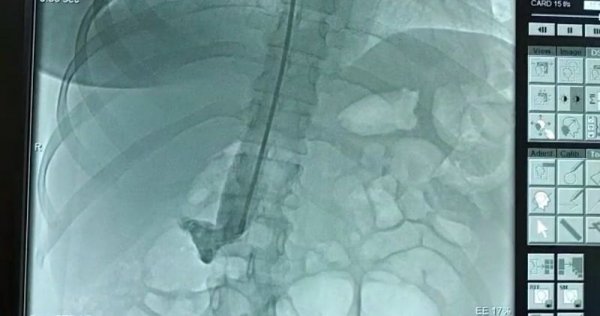

По данным пресс-службы Мангистауской областной больницы, у недавно родившей женщины диагностировали острый глубокий сосудистый тромбоз левой голени с признаками флотации.

- Если бы пациентка промедлила с обращением к врачам, могли быть серьезные последствия вплоть до наступления тромбоэмболии. Врачи вовремя предотвратили заболевание, установив кава-фильтр в нижнюю полую вену. Операция прошла успешно, - констатировал врач-кардиохирург Ернур Ордабаев.

- Тромб, образовавшийся в глубоких венах голени, может с током крови переместиться в легочную артерию, вызвав частичное или полное нарушение кровотока в ней. В такой ситуации человек умирает. Поэтому мы установили кава-фильтр и снизили уровень угрозы заболевания тромбоэмболией, - пояснил врач.

Операция длилась порядка 15 минут. Вместе с врачом-кардиохирургом Ернуром Ордабаевым ее проводил интервенционный кардиолог, аритмолог Курбанали Сабдинов.